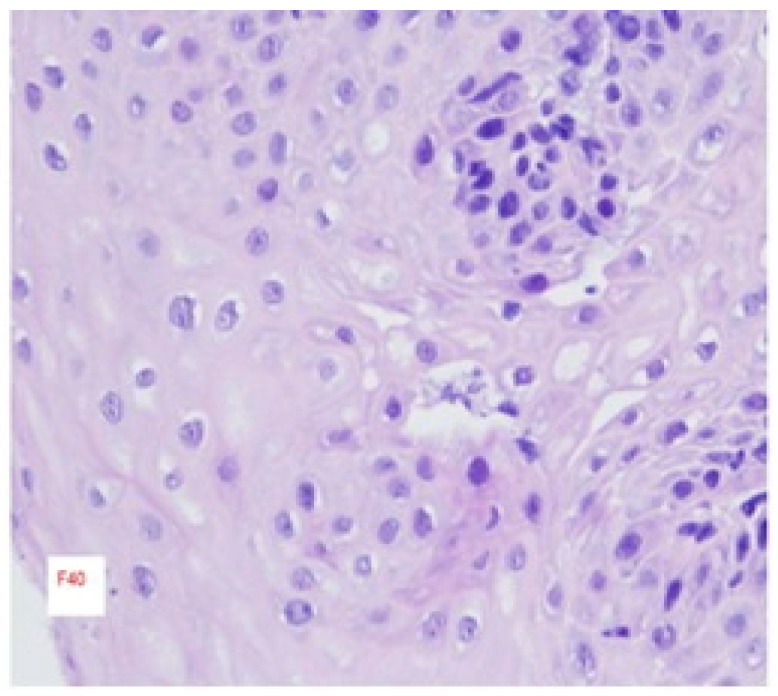

Background: Eosinophilic esophagitis (EoE) is a chronic, immune-mediated esophageal disorder characterized by Th2-driven inflammation. Clinically, it manifests as esophageal dysfunction, including dysphagia and food impaction, and is frequently associated with atopic comorbidities. Methods: Diagnosis is established via histologic confirmation of ≥15 eosinophils per high-power field (hpf) on esophageal biopsy. Clinical presentation varies, ranging from subtle dysphagia to severe complications necessitating urgent endoscopic intervention. Results: Disease progression is characterized by esophageal remodeling, encompassing fibrosis, angiogenesis, and muscular hypertrophy. Management strategies require individualized, long-term approaches aimed at symptom control and prevention of structural complications. Discussion: Advances in the last decade have refined diagnostic criteria, standardized endoscopic scoring systems, and introduced novel therapeutic agents, including biologics. This review synthesizes current evidence regarding epidemiology, clinical manifestations, diagnostics, and therapeutic strategies.